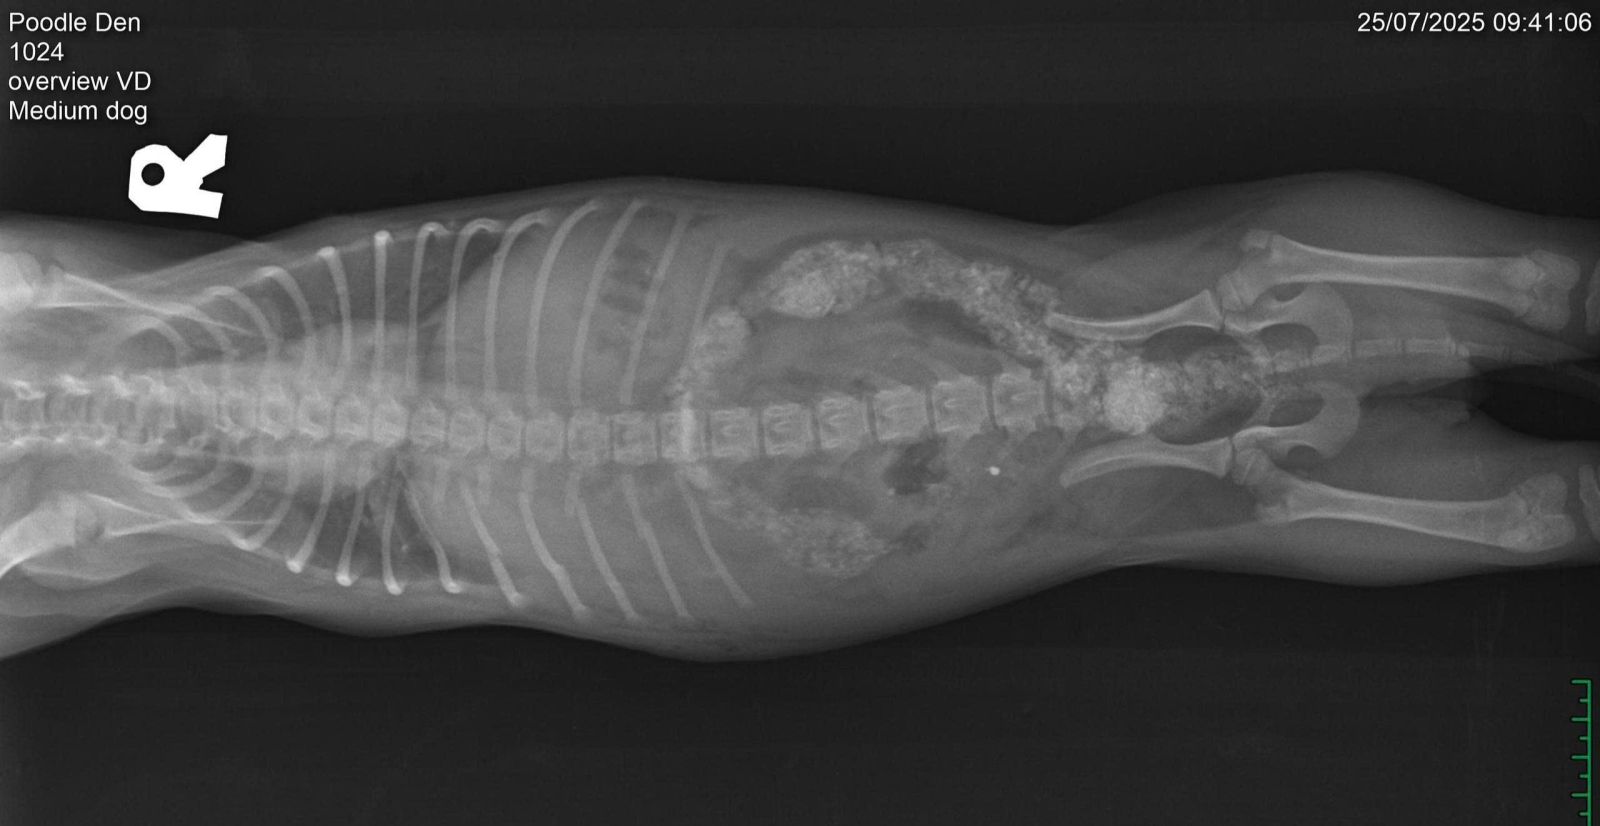

Băng bó cho cún cưng bị chó hàng xóm cắn gãy xương sườn